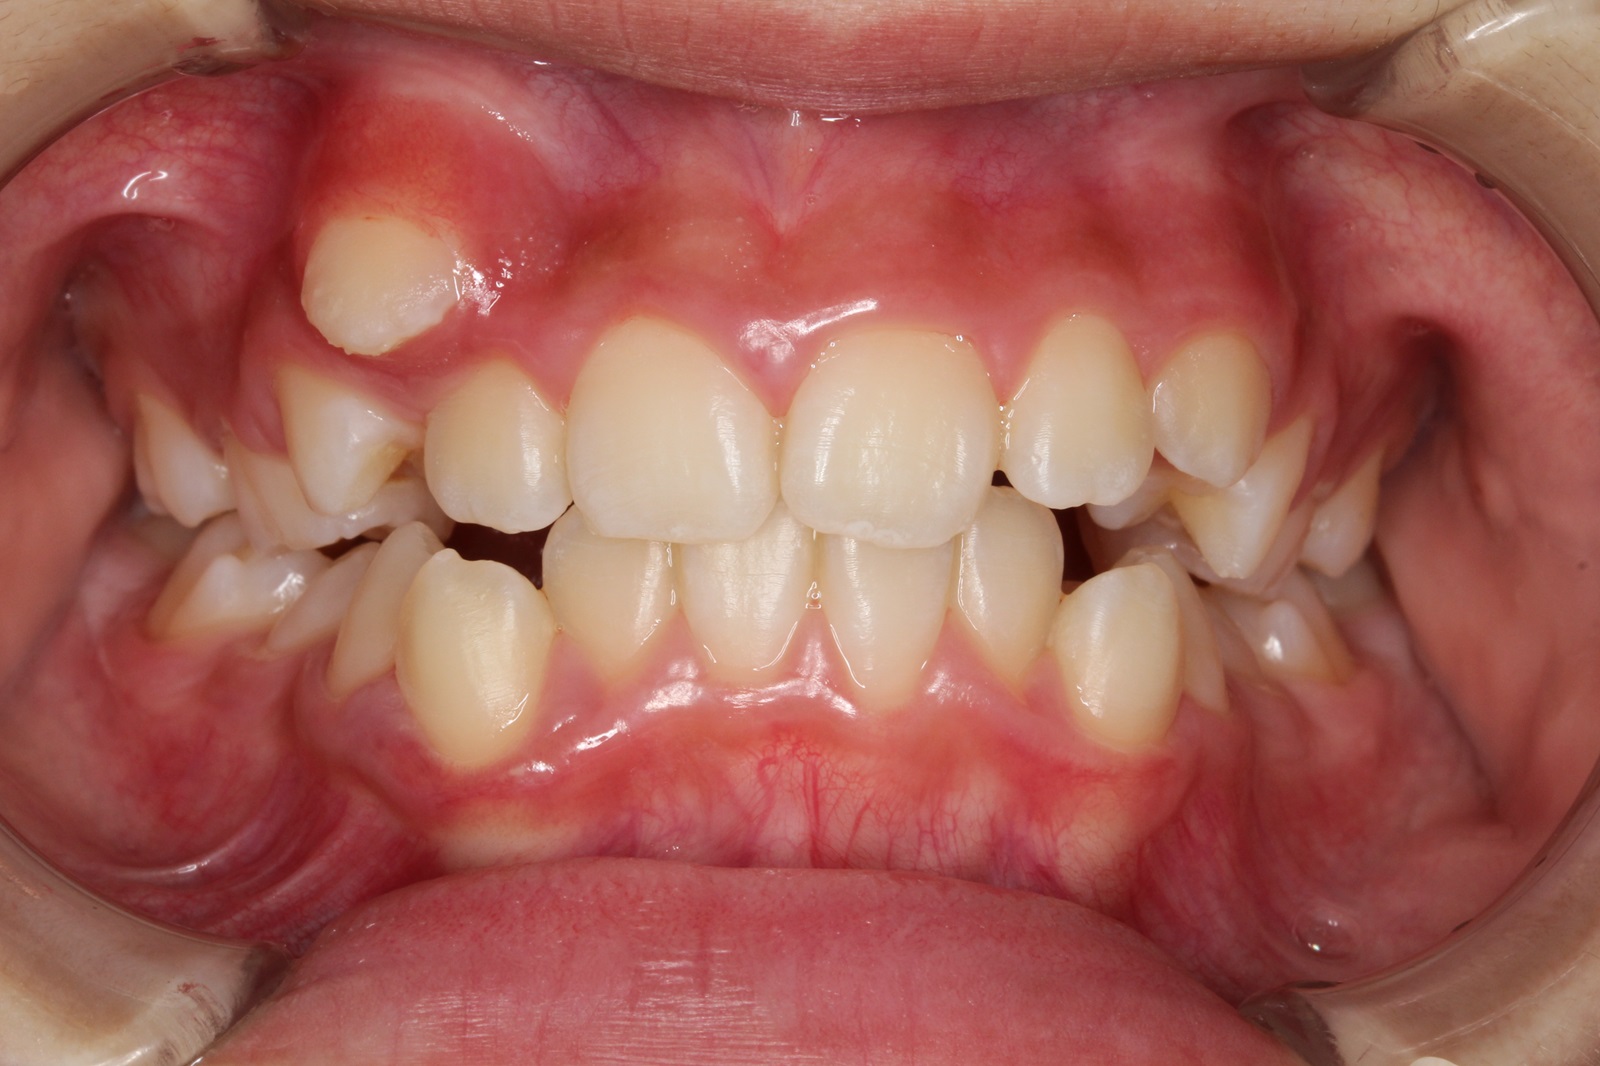

歯がデコボコに並んだ歯並びのことを「叢生(そうせい)」と言います。「乱ぐい歯」という名前でも知られています。叢生の歯並びの中で、よく知られているのが、上顎の犬歯が前方に突出している「八重歯」です。八重歯は可愛らしいイメージに捉えられることもありますが、歯並びとしては良くない、デコボコ歯並びの一種です。

叢生の原因は、顎の骨が小さく、歯が並ぶための十分なスペースが確保できないことが挙げられます。

叢生による問題は、見た目だけではありません。次のような様々な「リスク」があります。